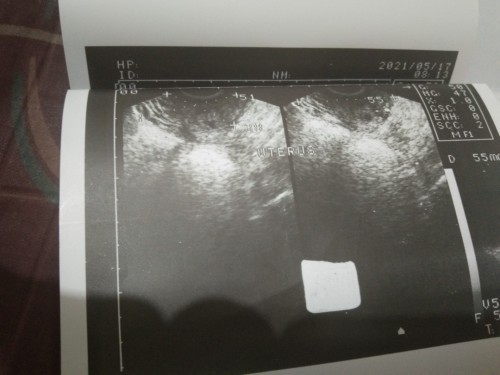

ganyan sakin last 2019 lahat ng test ko positive, sa ihi twice done pa sa micro, blood test, urine test puro positive pero wala din makita sa tvs ko, nagbi-bleed din ako non hanggang sa kakadugo ko nag-negative nalang. And now eto na naman nag PT ako nung march 11 negative pa inulit ko nung 16 faint lines then nung 22 may spotting ako so pt ulit ako faint lines pa din tapos masakit ang puson ko at balakang so kanina pagkabalik namin dito sa manila from mindanao nagpacheck up ako positive pa din sa PT pero malinaw na sya then nagpa tvs ulit ako wala nakita so after 3 weeks babalik ako para ulitin yung tvs sana lang wag matulad nung 2019 nagdiretso regla nalang hanggang sa magnegative na 😭 Masyado na kase malaki agwat ng panganay ko 12 years old na sya and nag-iisang anak ko, sana talaga sa pagbalik ko may makita na at sana mag-stop na ng spotting.

Magbasa paxge po kac nagtataka po kami negative sa Ultrasound tas sa PT is always positive kaso sabe sakin ng Dr.nagiimagine lang daw...nakaka lang talaga ung OB na un kac impossible namn na Positive sa PT and Home pregnancy q tas ultrasound is wala...cge po next month po aq magpaTVS...salamt po sa advise

yes. ganyan din sakin, naka 6 pt ako positive lahat. nung nagpacheck ako wala pa makita. kasi early pregnancy. pinabalik ako ni doc after 3 weeks and ayun kita na sila. twins pa 😅 going 8weeks na ko ngayon hehe

Baka too early pa po kaya di pa madetect sa ultrasound. Kadalasan pag ganyan pinaparepeat utz after few weeks.

Too early pa po. Same sakin early pregnancy wla pa nakita sa tvspero pg balik q nakita na si baby 6 weeks